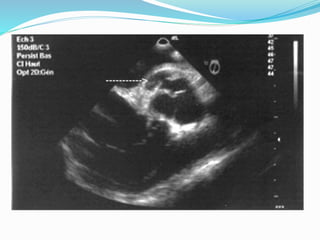

Echocardiographie doppler :

Examen clef, permet :

Diagnostic positif:

- Séparation diastolique des valves aortiques.

- Fluttering diastolique mitral.

-Visualisation de la régurgitation au doppler couleur.

- Quantification de la régurgitation :

- Diamètre du jet à l’origine, vena contracta > 6 mm.

- Temps de semi décroissance du gradient VG-Aorte (PHT < 350

ms).

- Vitesse télé-diastolique au niveau de l’isthme aortique >

20cm/s.

- Evaluation quantitative par l’analyse de la zone de convergence

(PISA).

- IAo sévère si : SOR > 30 mm², VR > 30ml, FR > 50 %.

- Retentissement sur le VG : - Dilatation (DTD, DTS),

hypertrophie (PP, SIV), fonction VG (FE, FR).

- Rechercher de lésions associées :